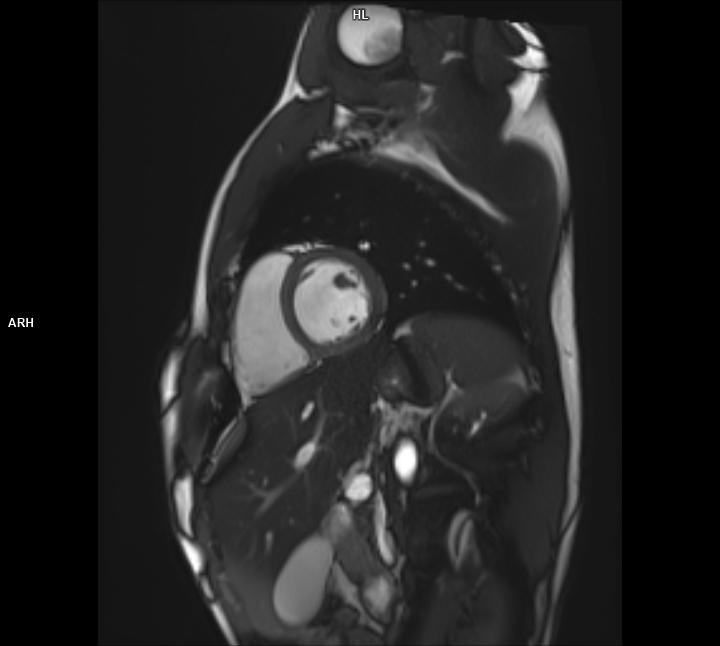

Kardiyolojik Değerlendirme: Kalp dokuları ve damar yapılarının incelenmesinde üstün hassasiyet sağlar.

Kompleks vakaların (örneğin beyin tümörleri, kalp anomalileri) değerlendirilmesinde tercih edilir.